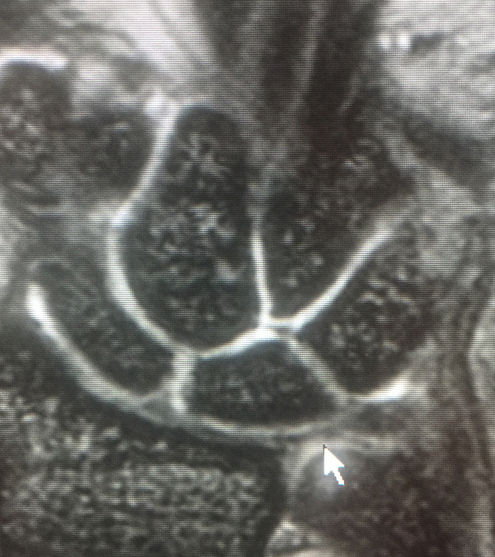

Musculoskeletal Imaging

MRI

There are many reasons your doctor may want Musculoskeletal Imaging. These include investigating the causes of joint and bone pain and conditions such as arthritis, tendon and ligament tears, meniscal tears, fractures, bone tumors and bone or joint infections.